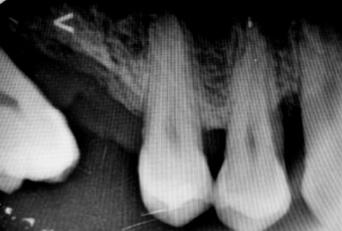

Figura 3. Protocolo de fresado quirúrgico: a) fresa piloto sentido horario, b) comprobación radiográfica, c) RX pin de paralelismo, d) fresa 2.3 sentido antihorario, e) comprobación radiografía periapical de posición y elevación del piso de seno, f) fresa 3.2 a 9mm con elevación evidente, g) verificación de profundidad con sonda del kit de implantes, h) colocación de injerto de hueso NovaBone, i) vista del hueso en el lecho quirúrgico j) fresa final diámetro 4.3, k) RX de comprobación de fresa 4.3 y l) RX de implante e injerto colocados.

Entre cada cambio de fresa, se verificó radiográficamente la dirección y profundidad del fresado. Finalmente, se completó el protocolo con el uso de la fresa de 4.2 mm de diámetro hasta alcanzar una profundidad final de 9 mm. Se obtuvieron imágenes radiográficas que evidencian la correcta colocación del injerto en la elevación lograda (ver Figura 3).